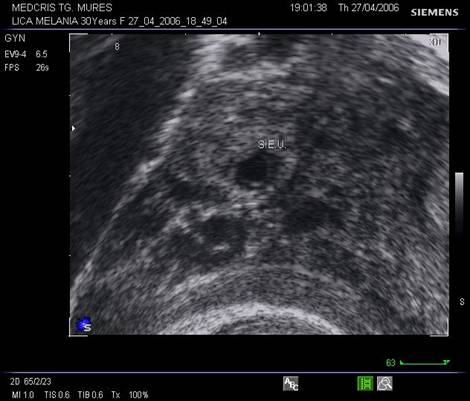

Fig nr 63

Aceeasi sarcina extrauterina oprita in evolutie ca in fig precedenta, marita cu

zoom. Se observa ( cu sageata ) un

embrion pe cale de liza ,situat decliv in sacul gestational .